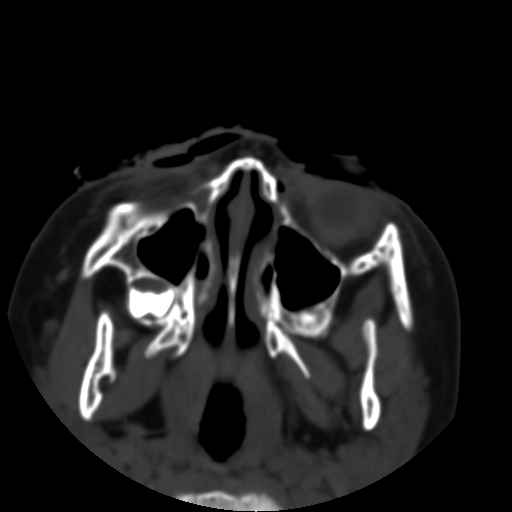

以下是引用深泽交通医院在2009-10-16 8:25:00的发言:[br]右眼环出血伴异物

以下是引用卜一在2009-10-16 15:01:00的发言:[br]右眼球挫裂伤伴异物!

以下是引用拾荒者在2009-10-17 18:38:00的发言:[br]鼻面部皮下积气,右侧睑缘及眼球壁高密度异物影,左侧眼球壁晶状体内侧缘处是圆形低密度影。低密度异物?应提请眼科医生注意。